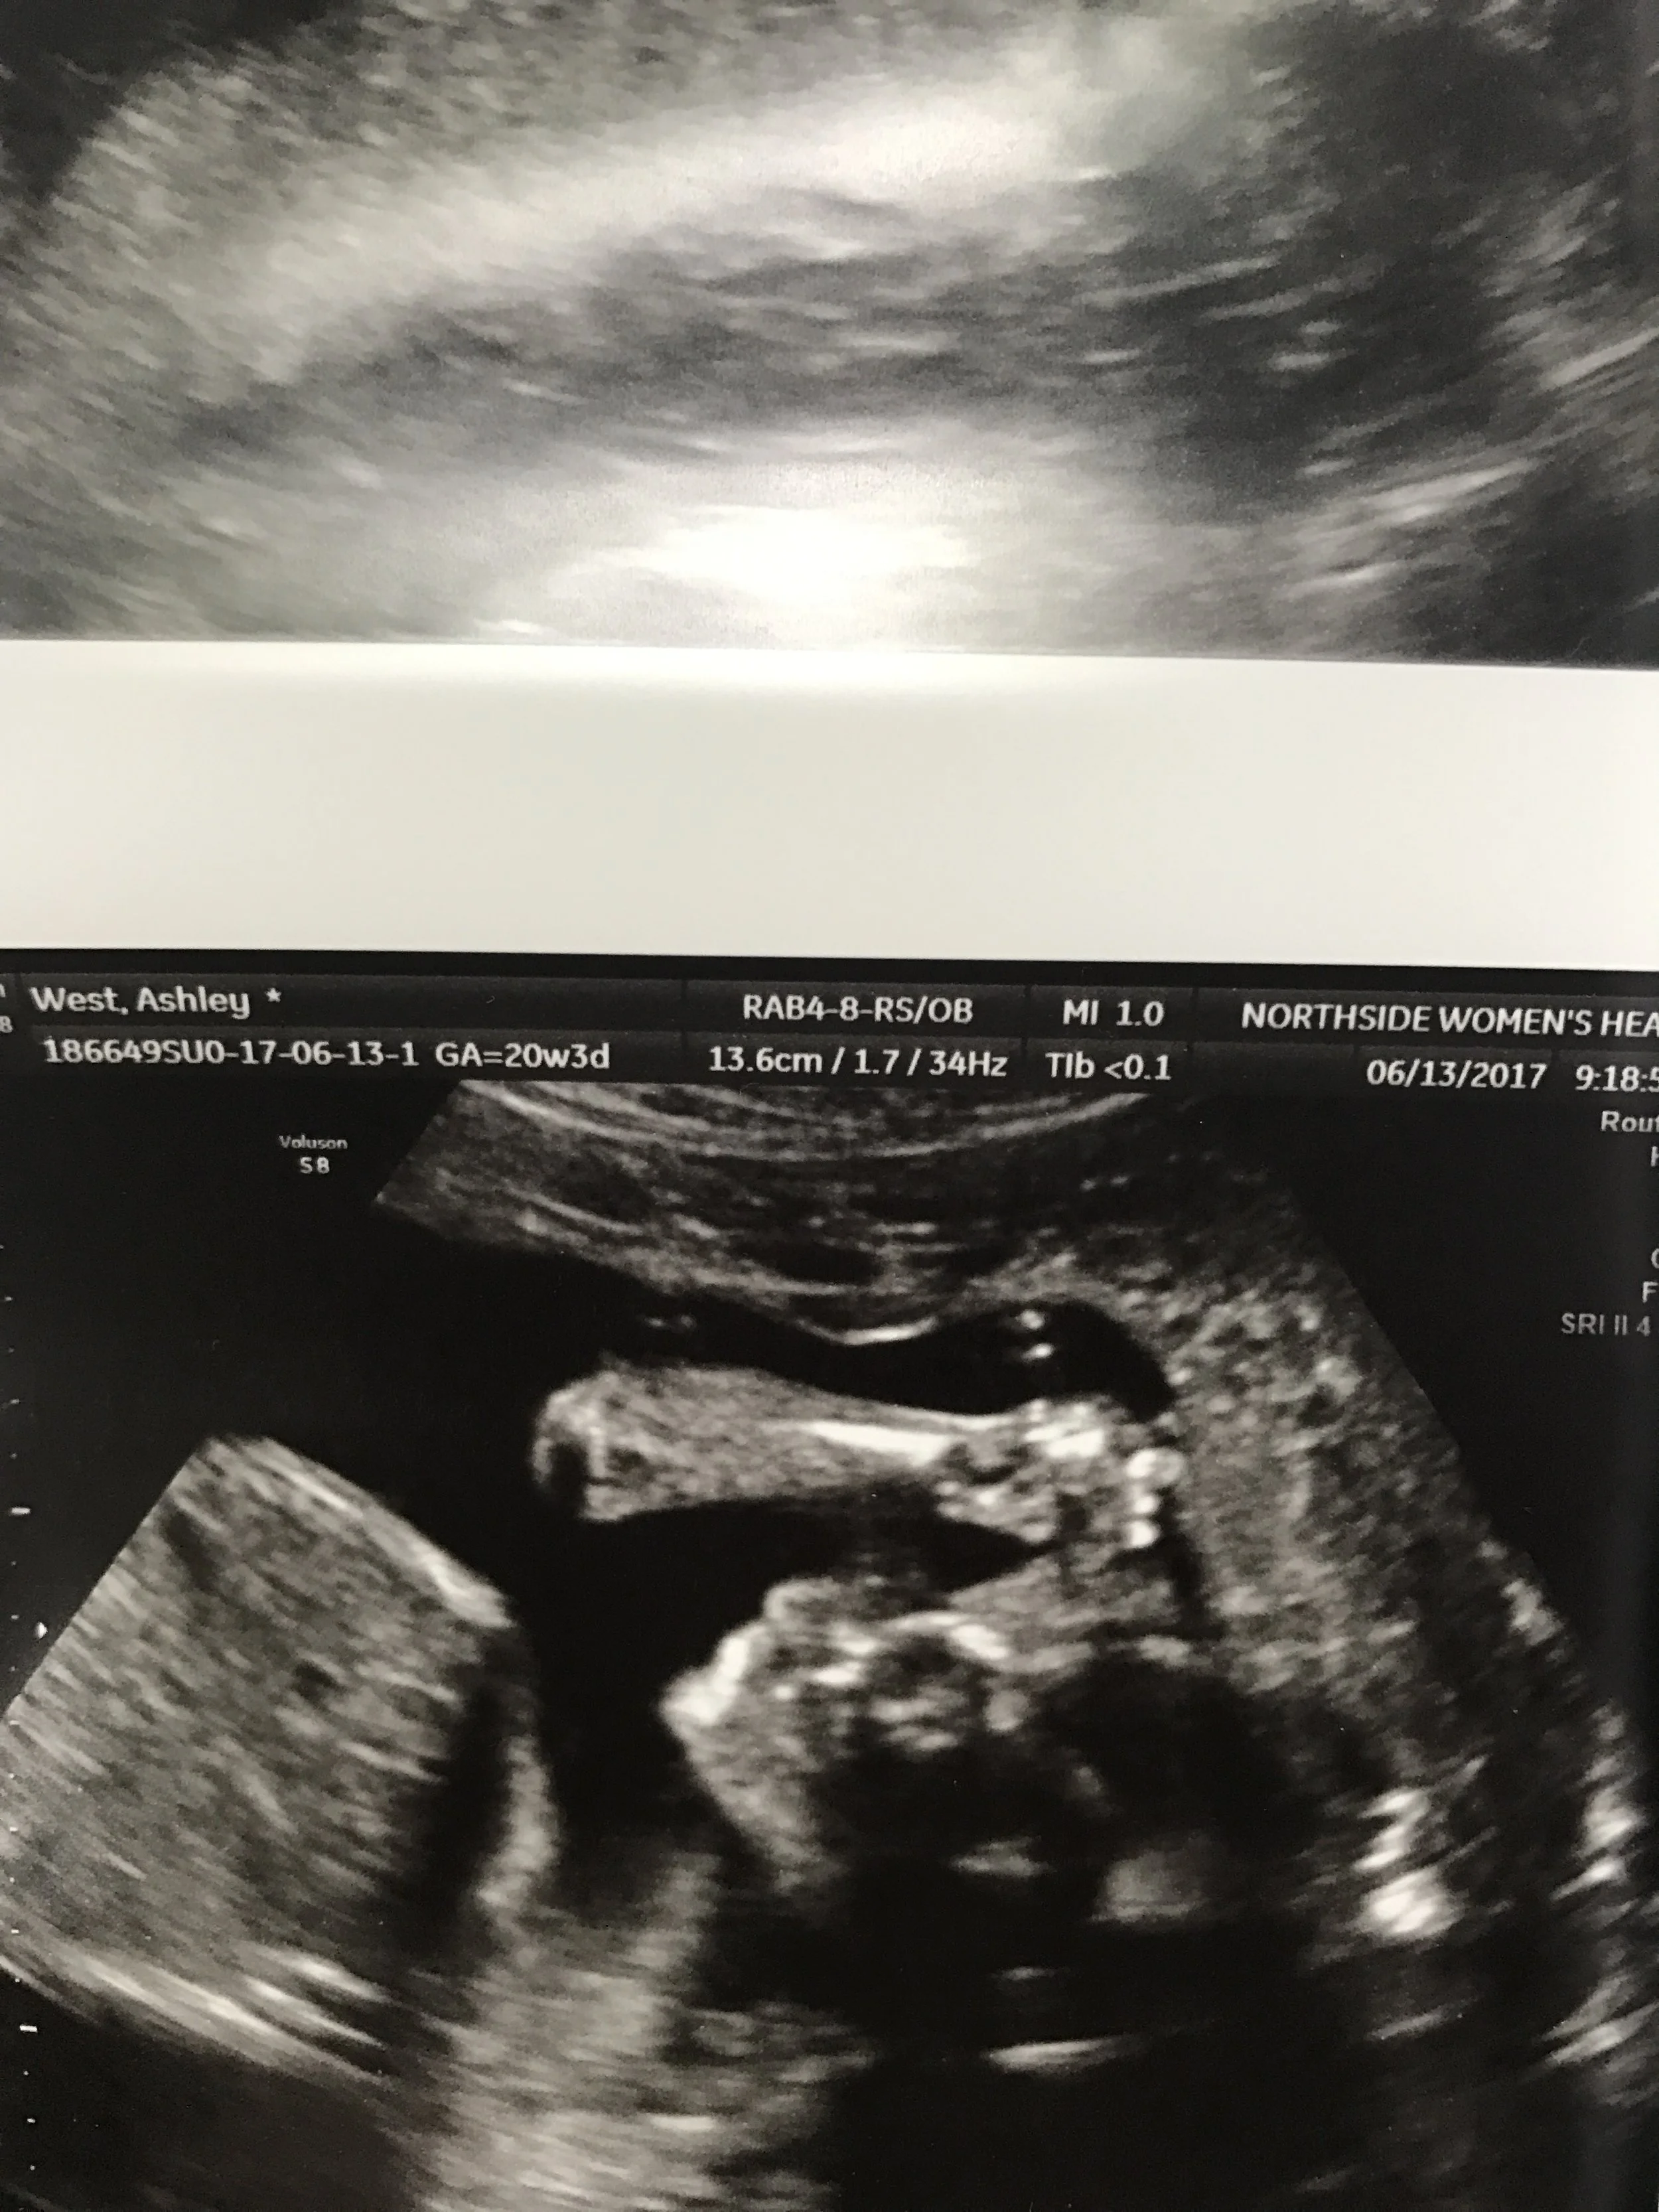

See his little face!?!? He's holding up his arm. HOW DO I LOVE HIM SO MUCH ALREADY. 20 week anatomy scan.

Now can we talk about BABY?! My last post we had just had our 16 week gender ultrasound. He looked amazing then and we were SO relieved and excited. Our anatomy scan was scheduled for 20 weeks. I was nervous for it, but not as nervous as our last ultrasound. The tech had assured us he was growing perfectly and right on track. We got amazing news again! They checked all the chambers of his heart and all of his little parts, according to them he is perfect. Aside from a few of my own challenging symptoms, baby has been wonderful every time. We've gotten a perfect report at each visit and that is just the most amazing feeling in the world.